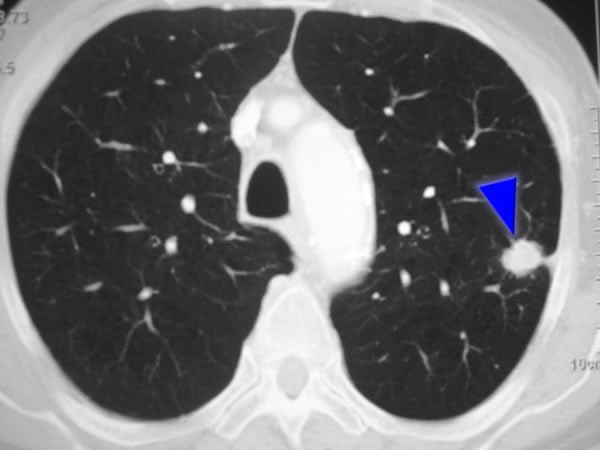

Un nódulo pulmonar (o masa cuando es mayor a 3 cm) es un área anormal que a veces se descubre durante una tomografía computarizada (CT) del pecho. Estos estudios se realizan por muchas razones, como parte de la detección del cáncer de pulmón, o seguimiento de algún cáncer de otra región (ejemplo mama, osteosarcoma, etc.), o para examinar los pulmones si usted presenta síntomas. Así lo explicó en una entrevista el Dr. Gary Kosai Vargas Mendoza, reconocido Cirujano de Torax en la ciudad de Mérida.

En este caso, el Dr. Gary Vargas Mendoza destacó que el siguiente paso con más frecuencia es repetir una tomografía computarizada para saber si el nódulo está creciendo con el pasar del tiempo. El tiempo que transcurra entre los estudios por imágenes podría variar desde varios meses a un año, dependiendo de si su médico sospecha que probablemente el nódulo sea cáncer. Esto se basa en el tamaño, la forma y la ubicación del nódulo, así como si parece ser sólido o lleno de líquido. Si al repetir un estudio se revela que el nódulo ha crecido, su médico también podría requerir otro tipo de estudio por imágenes llamado tomografía por emisión de positrones (PET) que a menudo puede ayudar a determinar si se trata de cáncer.